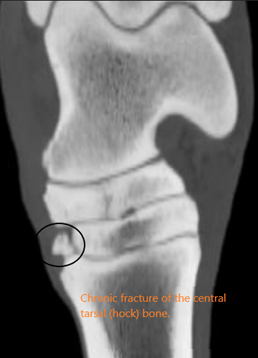

- Gold standard for bone changes (especially subtle bone changes)

- Bone chips and fracture lines